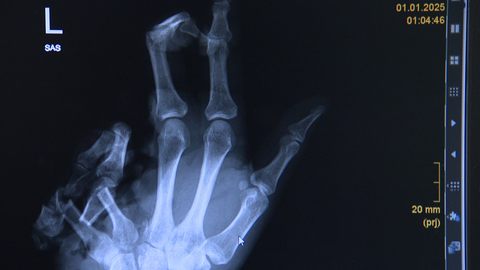

Röntgenbild der Hand des Mannes, der zwei Finger verloren hat.

Dem Mann fehlt nach Silvester der Ringfinger und der kleiner Finger.

Dabei hatte ein 33-Jähriger offenbar den Finger verloren. Der Mann wurde im Marienhospital noch in der Silvesternacht behandelt. "Er hatte eine komplett zersprengte Hand mit einem fehlenden Finger, ein zweiter Finger hing noch dran, war aber nicht mehr durchblutet", sagt Oberärztin Magdalena Lewicki. Der zweite Finger musste deshalb amputiert werden, erklärt die Ärztin weiter. Auch der gefundene Finger konnte nicht wieder angenäht werden. Laut der Oberärztin hatten die Angehörigen des 33-Jährigen wohl nach dem Finger gesucht, ihn aber nicht finden können.